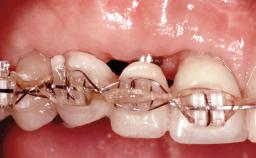

This 20-year-old woman was referred to our department in July 2006. Four months earlier, she had experienced dental trauma to the anterior maxilla when traveling in South America. The emergency treatment included emergency root canal treatment of teeth 12 and 11. Tooth 21 was also subjected to endodontic treatment later. At the initial examination, the patient was not in pain but reported increased mobility of tooth 12. The clinical examination revealed a high smile line, medium thickness of the soft tissue, and rectangular tooth forms. Discoloration of tooth 12 was evident. The periapical radiograph provided by the referring dentist indicated a fracture line at both teeth 12 and 11. A cone-beam computed tomography (CBCT) scan confirmed these fractures. No pathology was found to be associated with tooth 21.

| Interim Prosthesis during Healing | Removable Removable |

| Craniofacial/Skeletal Growth | In progress |